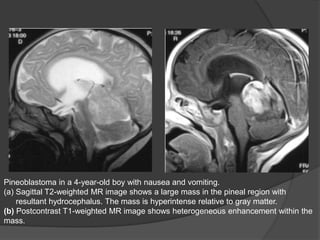

Pineoblastoma in a 4-year-old boy with nausea and vomiting.

(a) Sagittal T2-weighted MR image shows a large mass in the pineal region with

resultant hydrocephalus. The mass is hyperintense relative to gray matter.

(b) Postcontrast T1-weighted MR image shows heterogeneous enhancement within the

mass.